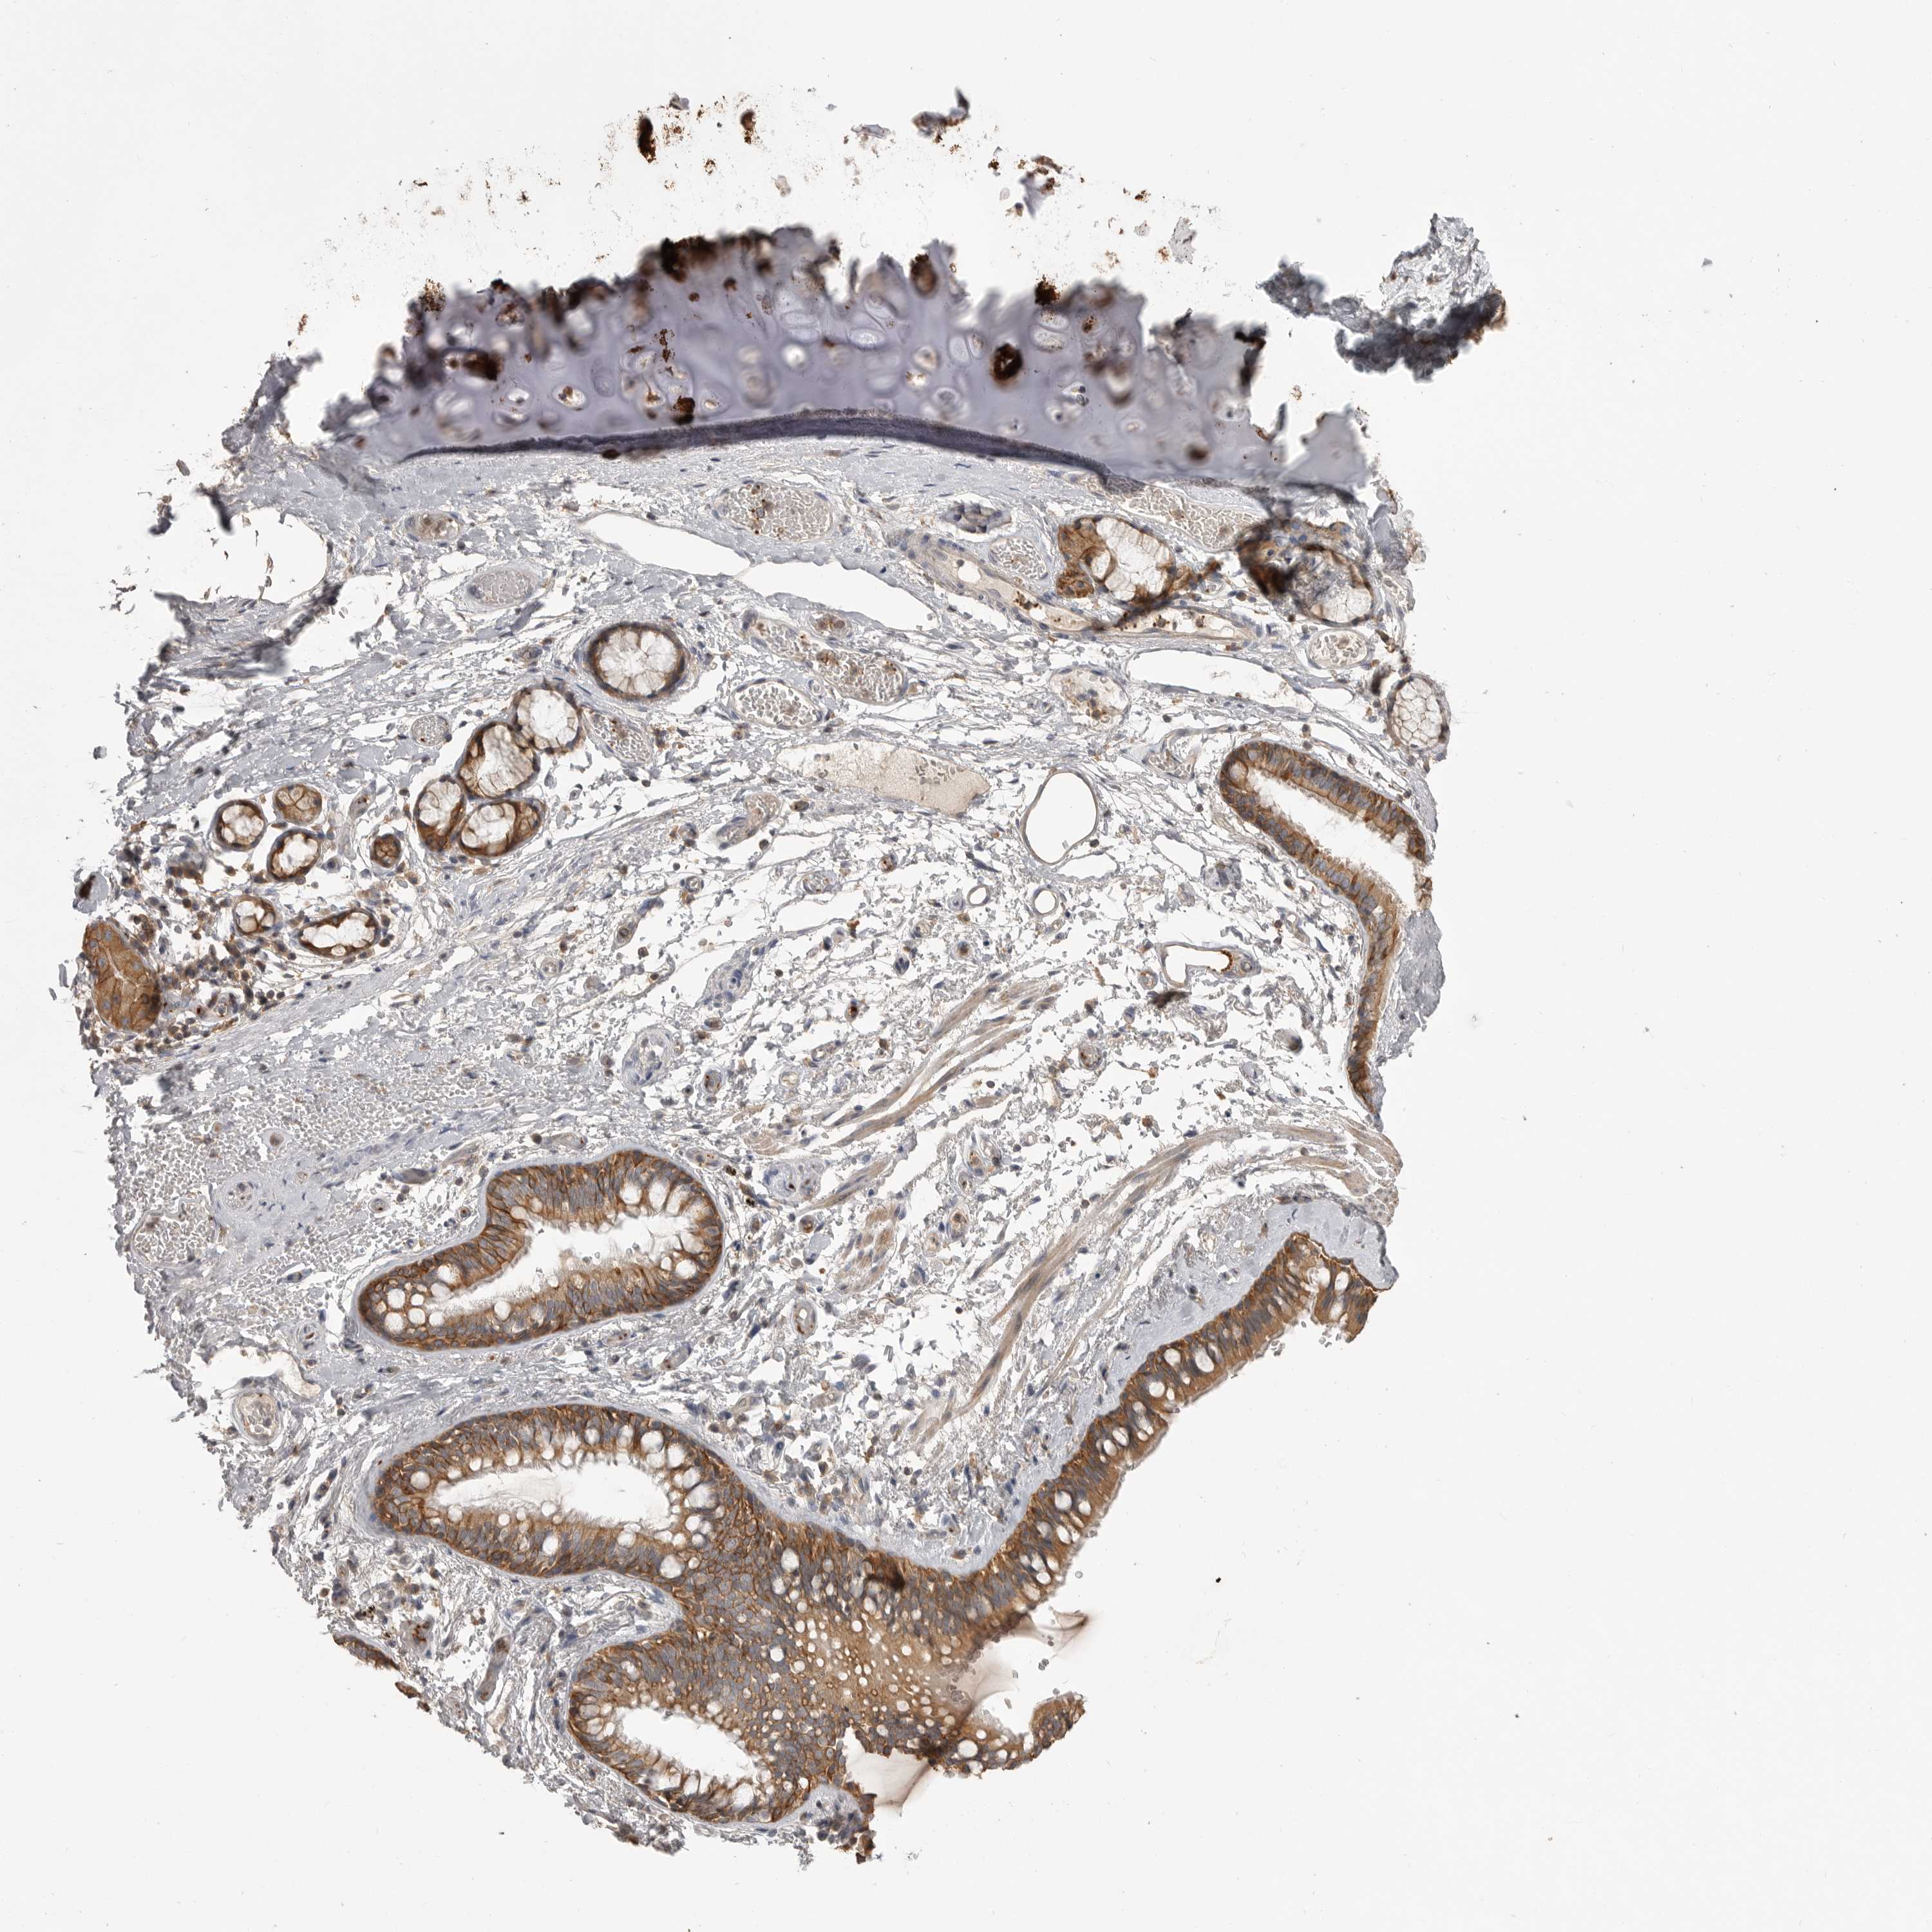

ADIPOSE TISSUE - Antibody stainingi

Antibody staining in the annotated cell types in the current human tissue is reported as not detected, low, medium, or high, based on conventional immunohistochemistry profiling in selected tissues. This score is based on the combination of the staining intensity and fraction of stained cells. Each image is clickable and will lead to virtual microscopy that enables deeper exploration of all samples and also displays staining intensity scores, fraction scores and subcellular localization as well as patient and tissue information for each sample.

Antibody HPA026980

Adipocytes Low